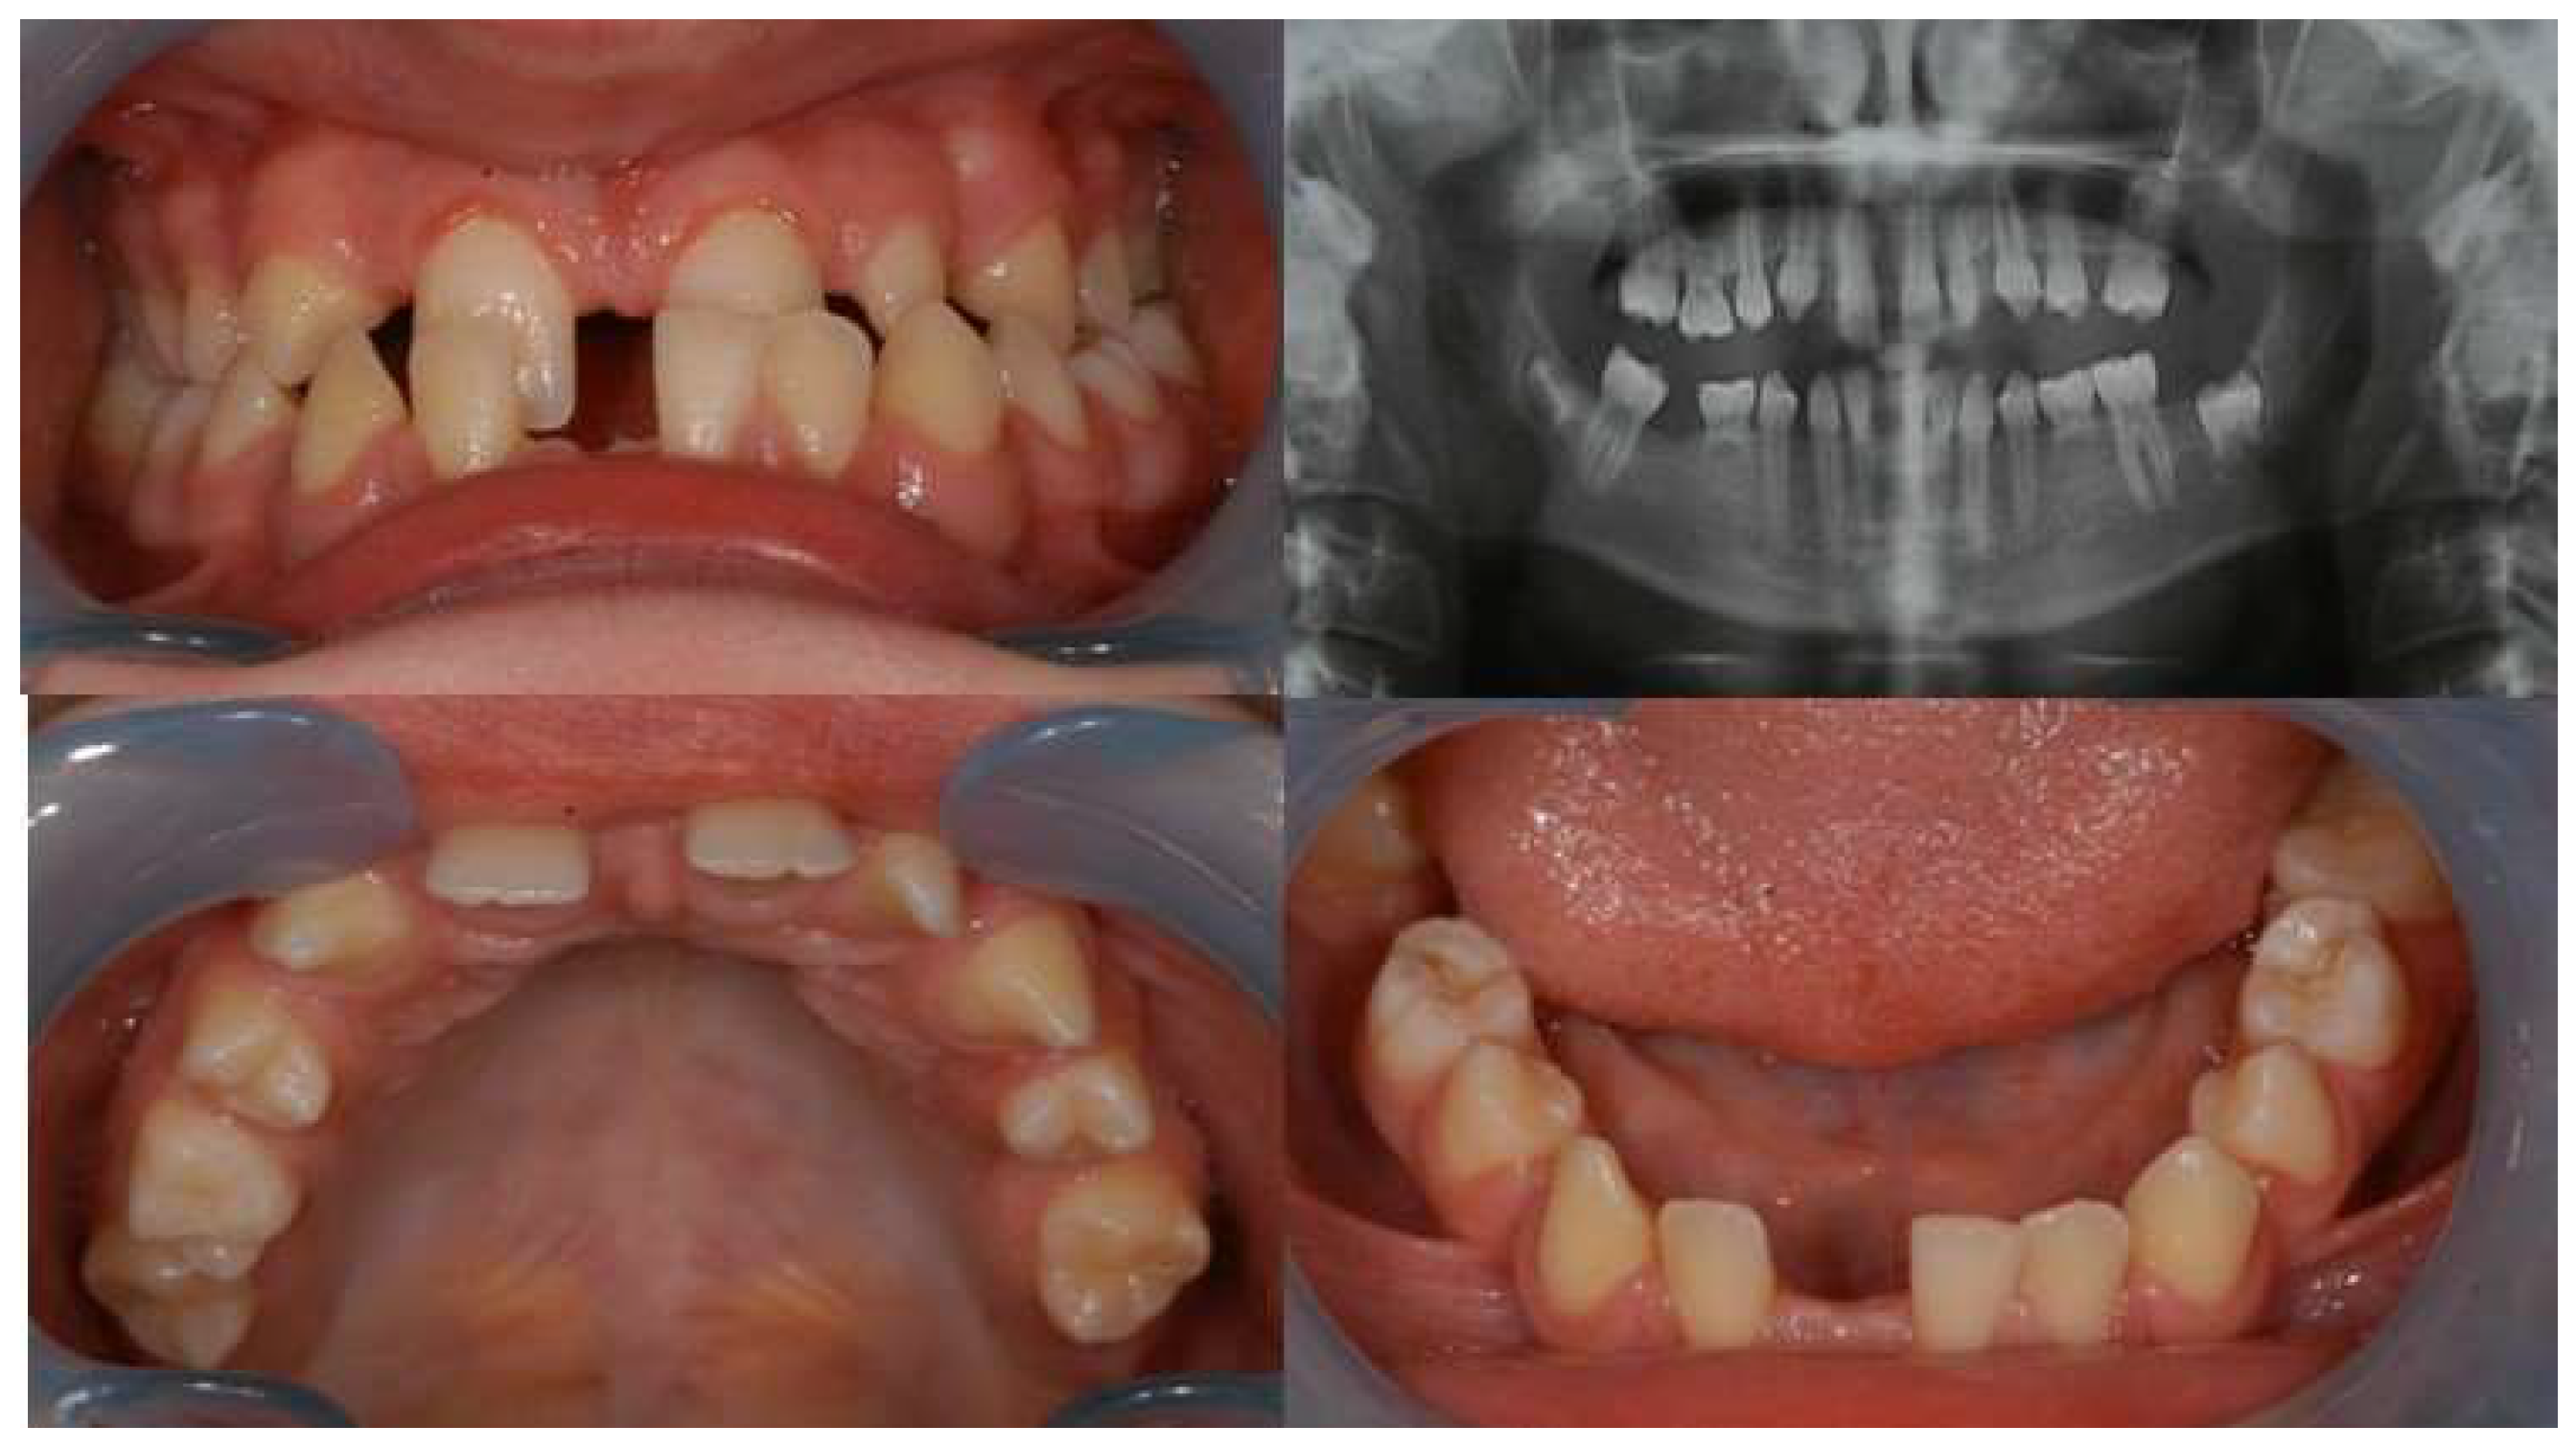

3. Results